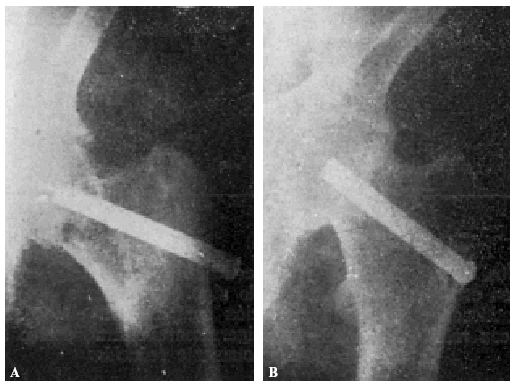

Teniendo en cuenta el mal estado general de la enferma se procede a la tracción continua, con ocho kilos de peso, mediante el procedimiento de Kirschner. A los ocho días ha mejorado extraordinariamente el estado general de la enferma, procediendo entonces a la osteosíntesis. Hay que advertir que la radiografía anteroposterior ha sido practicada antes de la completa penetración del clavo (fig. 2., A y B).

Figura 2. A: obs. núm. 8. Radiografía practicada antes de la completa penetración del clavo. Este está colocado en una posición demasiado craneal. B: Obs. núm. 8. El clavo fue colocado siguiendo la dirección del Kirschner superior. C: obs. núm. 8. El clavo se ha salido de la cabeza por su parte superior y su punta está situada a nivel de la parte superior de la caja cotiloide.

La radiografía (fig. 2., C) demuestra que el trocáncer ha ido ascendiendo, cortando el clavo el hemisferio superior de la cabeza hasta que, por haber chocado con la ceja cotiloidea, la ascensión del trocánter se ha detenido; pero entonces la pelvis ha basculado, ascendiendo la cresta ilíaca de este lado.

Actualmente nuestra mayor experiencia nos permite afirmar que el clavo, en este caso, había sido colocado demasiado cranealmente, y que, con toda probabilidad, una mejor exploración del estado general de la enferma nos hubiera indicado la inoperancia de la intervención.